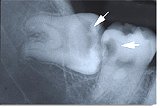

親知らずの虫歯

親しらずと前の歯の間から虫歯に

なります。(矢印の部分) |